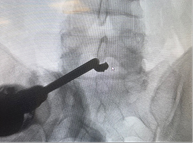

15.07.2025 г. проведена операция: эндоскопическая бипортальная ревизия, санация, удаление осколка из межтелового промежутка на уровне L5-S1 позвонков. Операция выполнена через два минимальных разреза по 0,7 см на уровне ранения. Под контролем флюороскопии в соответствии с методикой сформирован порт для эндоскопа и второй порт для рабочего инструмента. Операция выполнялась в водной среде под постоянной ирригацией физиологическим раствором. В ходе операции осуществлен атравматичный бескровный доступ к проблемному уровню без скелетирования (без рассечения) паравертебральных мышц. При помощи специального эндоскопического инструментария поэтапно, в соответствие с методикой, визуализирован проходящий S1 корешок и дуральный мешок, задняя продольная связка, осуществлен доступ к осколку. Последний выделен при помощи Г-образного крючка и удален при помощи конхотомов. Выделение и удаление осколка не сопровождалось тракцией невральных структур. Ход операции, начиная от доступа, внешний вид интраоперационной раны до и после удаления осколка представлены на фото.

Рис. 2. Этап доступа и внешний вид операционной раны кожи и на ЭОП-контроле.